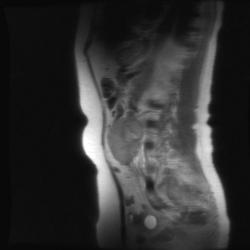

T1 ВИ Axial после введения контрастного препарата